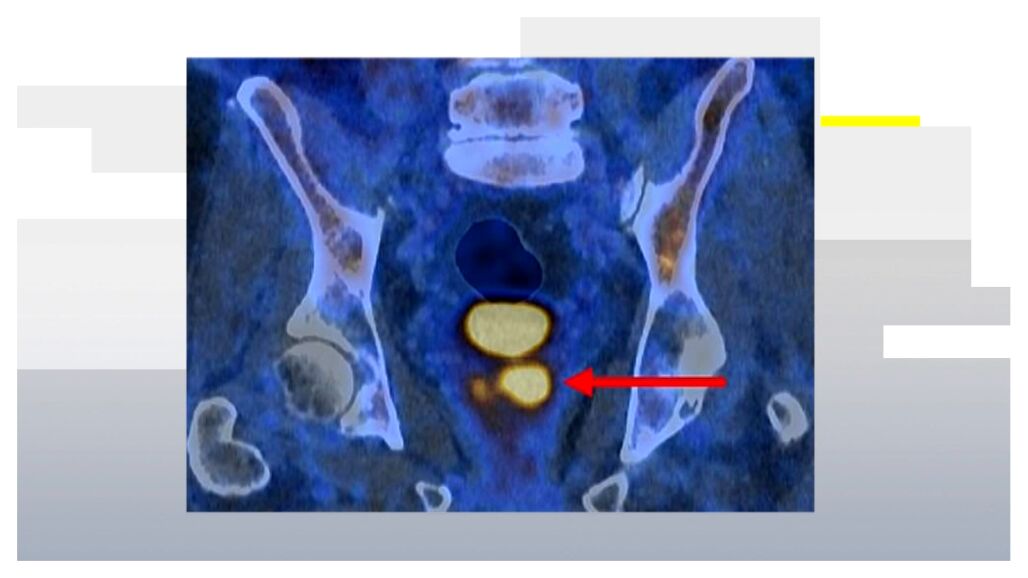

La técnica utiliza una molécula capaz de unirse a las células del cáncer de próstata. Cuando esto ocurre, esas células se vuelven visibles en la imagen del escáner.

En la práctica, aparecen como puntos brillantes en la prueba de imagen, lo que permite a los especialistas identificar con mayor precisión los tumores potencialmente más agresivos.

El doctor James Buteau, médico nuclear del Centro Oncológico Peter MacCallum, explica el funcionamiento de esta herramienta: "La tomografía PET/TC con PSMA ilumina las células del cáncer de próstata de forma notable, especialmente en los cánceres más agresivos. Es raro ver imágenes tan potentes en la práctica clínica".